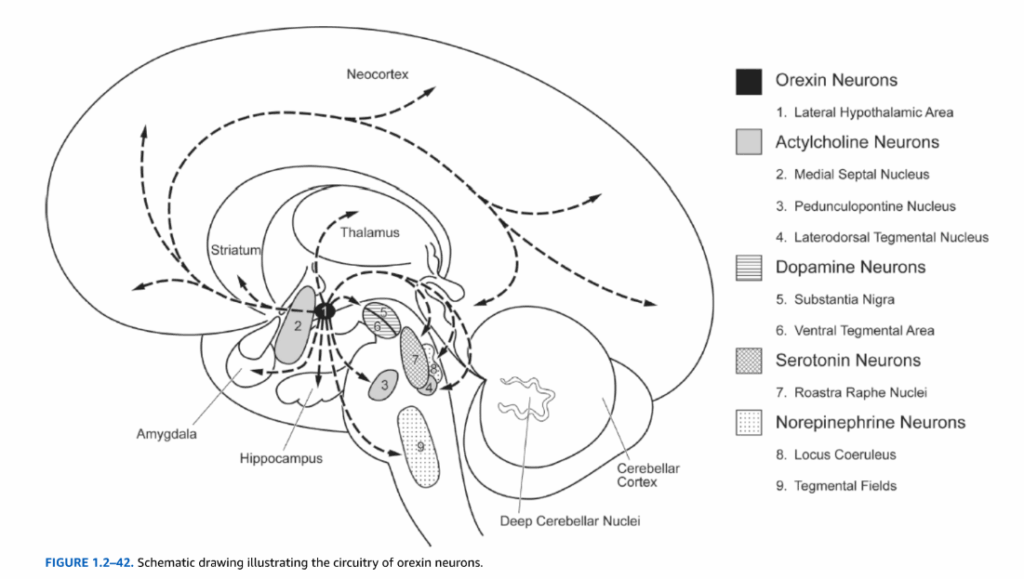

視床下部の外側部分は、内側前脳束の縦走線維の間に散在する低密度のニューロンを含んでいる。この領域は前脳、脳幹、脊髄の複数の領域と相互結合している。外側視床下部領域はまた、オレキシン神経ペプチドであるオレキシンAおよびオレキシンB(ヒポクレチンAおよびヒポクレチンBとしても知られる)を発現するニューロン集団を含み、これらは睡眠と覚醒に関与していると思われる。ヒト脳におけるおよそ70,000個のオレキシン産生ニューロンは、小脳を除く脳全体に投射している(図1.2-42)。オレキシンニューロンは大部分のモノアミン作動性核(すなわち、黒質、青斑核、背側縫線核)およびコリン作動性核(すなわち、内側中隔、脚橋被蓋核、外側背側被蓋核)に投射している。オレキシンニューロンはまた大脳皮質全体に広範な投射を持っている。オレキシン軸索の高密度を含む領域には、視床室傍核、視床下部弓状核、青斑核、背側縫線核が含まれる。睡眠と覚醒に関与する神経系(すなわち、青斑核、縫線核、外側背側/脚橋被蓋核)へのオレキシンニューロンの投射は、オレキシンニューロンがこれらの機能に参加していることを示唆している。動物およびヒトにおける多数の研究は、オレキシン欠乏がナルコレプシーの主要な原因であることを示している。例えば、オレキシン遺伝子を欠くマウスはヒトナルコレプシーに類似した生理学的症状を示し、ナルコレプシー患者の脳の死後検査では、オレキシン免疫反応性ニューロン数の85から95パーセントの減少が明らかになっている。

図1.2-42. オレキシンニューロンの回路を示す模式図。